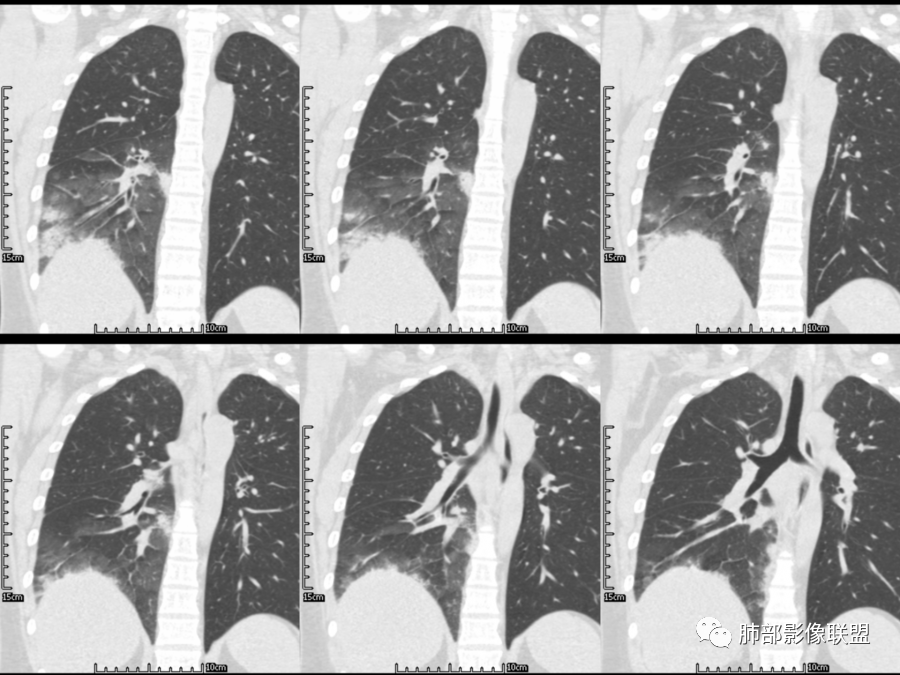

定位及定性

一切∮随缘

右肺胸膜下实变,病变跨多个叶生长,宽基底与胸膜相连,近端支气管穿行病灶内,并可见片状磨玻璃影,边界清,部分远端小支气管堵塞,支气管略有扩张,周围散发小结节,临床年轻女性,炎性指标高,发热六日,首先考虑感染性病变(肺链,奴卡,隐球,OP)鉴别淋巴瘤。

💓 蕊💓

年轻女性,无明显诱因发热,体温略高,起病较急,有畏寒,右下肺紧贴胸膜下片状实变影,部分融合,外围有结节影,性质比较单一,类似于蘑菇兄弟,病灶周围伴有晕,支气管进入近端扩张远端堵塞,常规考虑感染,肺炎链球菌、隐球菌。

红日东升

青年女性,发热咳嗽5天,炎症标志物升高。右肺下叶大片实变伴周围GGO,GGO内未见细网格,主体与胸膜平行,似多个病灶融合,实变区内见支气管部分进入,部分支气管受压狭窄,周围可见多发卫星病灶。支持炎性,考虑隐球感染,鉴别op。

薏米

年轻女性,急性起病,咳嗽,发热,黄痰,白细胞高,CRP基本正常,基础体健。CT提示右肺下叶实变,宽基底与胸膜相连,长轴平行于胸膜,可见支气管充气征,于病变中央截断,走形自然,胸膜下脂肪间隙可见,倾向于隐球菌,鉴别肺链,军团菌等。

景俊峰

年轻患者,右肺下叶大片状实变影,长轴与胸膜平行,内见含气支气管征,周围磨玻璃晕影。考虑感染性病变,隐球?

甄德强

病灶长轴与胸膜平行,边缘有晕,病灶融合趋势,支气管进入,走行自如,考虑隐球菌肺炎。

小兜

年轻女性,急性发病,咳嗽咳痰五天,炎性指标升高,右肺下叶胸膜下大片实变影,周围见磨玻璃影,边界清晰,长轴与胸膜平行,呈融合趋势,支气管进入走行自然,远端截断,考虑炎性,隐球菌可能。

秋实

年轻女性,发热,急性发病,白细胞高,右肺下叶大片实变,长轴与胸膜平行,内见支气管走行,远端截断,周围有晕,晕边界清,考虑感染,隐球可能,鉴别淋巴瘤。

周太狼

年轻女性,右肺下叶胸膜下多发实变、结节影,宽基底与胸膜相连,边缘模糊不清,实变内见支气管穿行,血象高,考虑感染性病变,大叶性肺炎?隐球?

丽

青年女性,发热咳嗽急性起病,右肺下叶大片状实变密度影,长轴平行于胸膜,边缘模糊可见磨玻璃影及高密度结节影,实变内可见支气管穿行,直达病灶远端,考虑感染性病变,隐球菌可能大。

月亮圆了!

右肺胸膜下实变,病变跨多个叶生长,相互融合,宽基底与胸膜相连,支气管气象,并可见片状磨玻璃影,边界清,炎性指标高,发热六日,考虑感染病变,链球菌?腺病毒待排。

王秀仙

右肺下叶大片状实变影,长轴平行于胸膜,边缘模糊可见磨玻璃影,支气管进入,部分近端阻塞,考虑感染性病变,隐球菌,鉴别大叶性肺炎。

三个石头

年轻女性,起病急,白细胞,C反高,存在感染。右下肺大片实变影,支气管充气征,长轴平行胸膜,似多个病灶融合,周围GGO,部分清,部分不清。考虑感染,隐球可能。

飞鹰行动

青年人,右肺多发团片状阴影,边缘模糊,周围可见磨玻璃影,内部有支气管空气征,考虑感染性病变,隐球菌感染可能。

蓝天白云

右肺下叶大片状实变影,从外向内,长轴平行于胸膜,边缘模糊,可见磨玻璃影,支气管进入,远端部分阻塞,考虑感染性病变,隐球菌,鉴别淋巴瘤。

流心明智

26岁,女性,发热、咳嗽5天。咳少量黄痰,起病急,病程短,白细胞及中性高,血沉及D-二聚体增高。胸部CT:右肺下叶大片实变,长轴沿胸膜分布,宽基底与胸膜接触,边界不清,周围GGO,部分团片影融合,病灶内可见支气管充气征,部分支气管进入病灶后阻塞。考虑:感染性病变,隐球菌?脓毒肺栓塞?鉴别:肺炎型肺Ca。

德芙~云味

年轻女性,右肺下叶一大片实变影,似有多个结节影融合,周围有晕,内见支气管充气征,部分支气管进入后截断,病变近胸膜,长轴胸膜平行,考虑炎性,隐球菌首先考虑。

慎独

青年女性,影像表现右肺下叶胸膜下大片状实变影,近端见充气支气管征,边缘见片状磨玻璃影,下叶背段尚可见一结节。考虑感染性病变,隐球菌感染可能。

Lenle董

右下肺大片实变影,空气支气管征,边缘GGO,小叶间隔增厚,周围有蘑菇兄弟,基底宽,与胸膜平行,考虑隐球菌感染,鉴别肺炎型肺癌。

一米阳光

晨读:年轻女性,右肺胸膜下实变影,平行于胸膜,边缘磨玻璃影,内见支气管充气征,走形自然,略扩张。考虑感染性改变,隐球,肺链。2月发病,病毒性肺炎要考虑。鉴别淋巴瘤。

弹指之间

晨读:年轻女性,发热咳嗽5天。白细胞计数升高。右肺下叶大片状高密度影,边缘模糊,有实变 GGO,其内见支气管气相、无受压变细,无枯枝表现,其近端支气管无异常,右肺下叶背段见结节状影,定性考虑:炎症,隐球菌感染可能,炎症型肺癌不支持。

宇宙星空

右下肺胸膜下大片状高密度影,其长轴与胸膜平行,病灶近端GGO模糊,部分支气管进入后阻断,支持感染性病变,考虑隐球菌